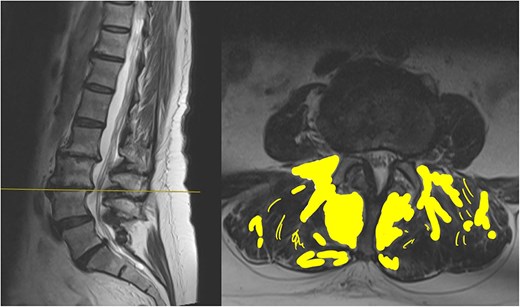

The MRI report detailed the vertebral bodies, discs, and spinal cord but did not comment on the surrounding spinal musculature. On review of the images, no clear impingement of the spinal nerves was seen (Fig. 2). It was, however, noted that there was significant fat infiltration of the paraspinal muscles (Fig. 3).

Sagittal and axial section at L3/4. The fat infiltration is highlighted in a yellow shade in this image.

The report had used the word degenerative on four occasions without acknowledging that this could be age-related. There was also no mention of the significant fat infiltration seen.

Fatty infiltration is a form of muscle sarcopenia. A sedentary job and lack of exercise can lead to weakening of the muscles, the changes of which can be eventually visualized on imaging. While spinal MRI is often discouraged unless clearly indicated, one advantage is its ability to detect fatty infiltration of muscles. Identifying such changes can reveal underlying muscular dysfunction, a potentially correctable problem, allowing for targeted rehabilitation.